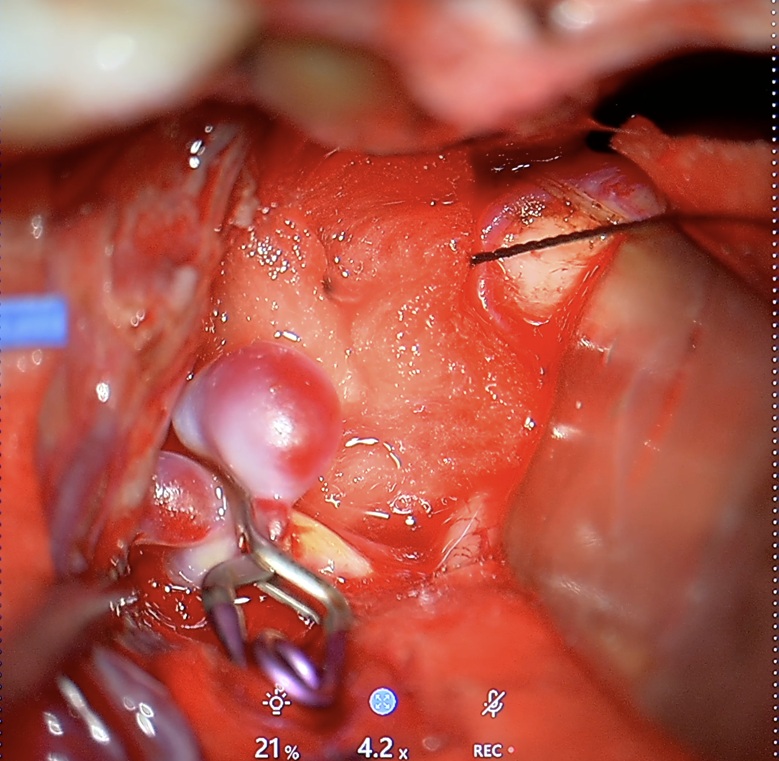

Klipsowanie chirurgiczne – metoda klasyczna

Jak przebiega zabieg?

Jest to operacja neurochirurgiczna, podczas której wykonuje się kraniotomię (czyli czasowe otwarcie fragmentu kości czaszki, aby uzyskać bezpieczny dostęp do mózgu). Pod mikroskopem operacyjnym neurochirurg zakłada tytanowy klips na szyję tętniaka, trwale odcinając dopływ krwi do jego wnętrza, przy jednoczesnym zachowaniu prawidłowego przepływu w naczyniu macierzystym (głównej tętnicy).